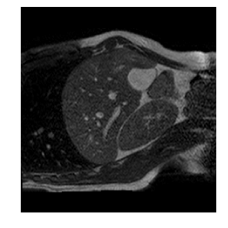

Qualitative results are shown in Fig. 4. We observe no large qualitative differences in the performances of MFIN and MFINc for either loss function. Since, MFINc-SSIM provides the best quantitative results, we show interpolated images from this method and compare them against SCIN-SSIM. Both methods perform well when the motion between the neighbouring images is low. This is reflected in the absence of any structures in the error images in Fig. 4.1. However, RMSE is lower for SCIN because it produces a denoised interpolated image, while MFIN carries over the noise pattern from the neighbouring known image. Whenever there exists high motion between the images being interpolated, SCIN produces blurry images and often misses image structures. This can be observed in cases 2-4 in Fig. 4. For all these cases, MFINc (and also MFIN) produces sharp images and largely preserves structures in the images. Fig. 4.2 shows a case where MFINc additionally has a much better performance with respect to image alignment. Fig. 4.3 shows a representative case, with small improvement in image alignment, yet worse RMSE and SSIM values for MFINc. Finally, Fig. 4.4 shows a case, where MFINc produces worse alignment of structures than SCIN.

9.16, 0.76 10.12, 0.74

3)

9.75, 0.85 12.94, 0.81

4)

a b c d e